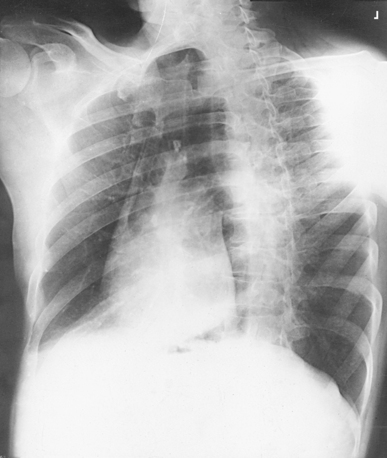

Structures shown: PA projection of the thoracic viscera shows the air-filled trachea, the lungs, the diaphragmatic domes, the heart and aortic knob, and, if enlarged laterally, the thyroid or thymus gland (Fig. 10-32). The vascular markings are much more prominent on the projection made at the end of expiration. The bronchial tree is shown from an oblique angle. The esophagus is well shown when it is filled with a barium sulfate suspension.

Structures shown: An AP projection of the thoracic viscera (Fig. 10-51) shows an image similar to the PA projection (Fig. 10-52). Being farther from the IR, the heart and great vessels are magnified and engorged, and the lung fields appear shorter because abdominal compression moves the diaphragm to a higher level. The clavicles are projected higher, and the ribs assume a more horizontal appearance.